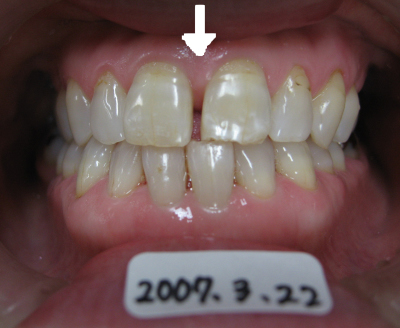

矢印の部分の隙間が気になる。

しかし歯は削りたくない。

歯と歯の間にプラスチックを流し込んで約10分で治療終了。

歯は一切削っていません。